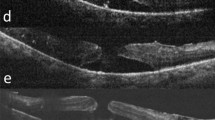

Four traction-related developmental processes were identified. Type 1 LMHs (8, 16%) developed from foveal avulsion caused by vitreomacular traction. Type 2 (32, 64%) and type 3 LMHs (5, 10%) formed from ruptured parafoveal and central foveal cysts, respectively. Progressive foveal thinning caused by epiretinal membranes (ERMs) without cystic changes led to type 4 LMHs (5, 10%). Retinoschisis developed before (9 eyes), after (10 eyes), or simultaneously with (6 eyes) the LMH formation. Structural progression was noted in 50%, 53%, 0%, 100% of patients with type 1–4 LMHs, respectively. Multivariable Cox proportional hazard model showed that greater residual foveal thickness (P = 0.001, adjusted odds ratio = 0.22, 95% confidence interval [CI], 0.08 ~ 0.56), and the absence of retinoschisis were protective against structural progression. Multivariable linear regression showed that poor baseline visual acuity (P < 0.001, β = 0.74, 95% CI 0.41 ~ 1.07) and type 4 LMH predicted worse visual outcomes.